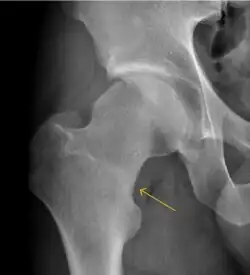

Slipped capital femoral epiphyses (SCFE) usually affect 11- to 14-year-old adolescents (Figure 4). Radiographs may show widening and irregularity of the physis and posterior inferior displacement of the capital femoral epiphysis. On the AP view Klein’s line, tangent to the lateral aspect of the femoral neck, does not intersect the femoral head indicating that it is displaced. SCFE may compromise the blood supply to the femoral head and cause avascular necrosis, mainly when there is instability between the fragments.[1]

Synovial chondromatosis can be confidently diagnosed by X-ray when calcified cartilaginous chondromas are seen. However, other synovial proliferative processes, such as pigmented villonodular synovitis, require MRI for accurate diagnosis, although noncalcified synovitis can be suspected in radiographs by indirect signs, such as soft tissue swelling and/or erosions in the femoral head, femoral neck, or acetabulum (Figure 7).[1]

Figure 7: